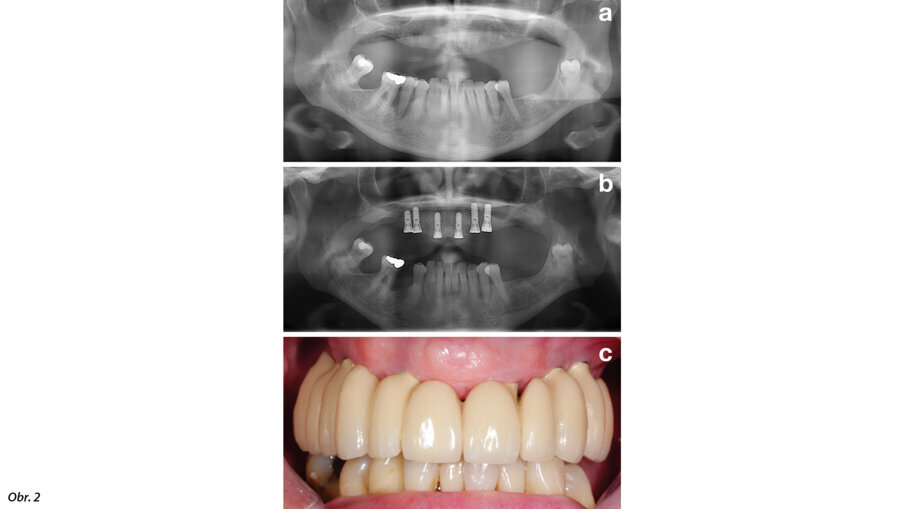

První část (tj. fáze před ošetřením) má za cíl perfektně připravit pacienta na samotné zavedení implantátu na základě vyhodnocení všech potenciálních rizikových faktorů, především se zaměřením na ten nejvýznamnější: zajištění stabilní parodontální situace (obr. 2).

Obr. 2: Před zaváděním implantátu by měla být zajištěna stabilní parodontální situace. Pacient před parodontologickým ošetřením (a), po parodontologickém ošetření a zavedení implantátu (b) a po nasazení protetické náhrady (c).